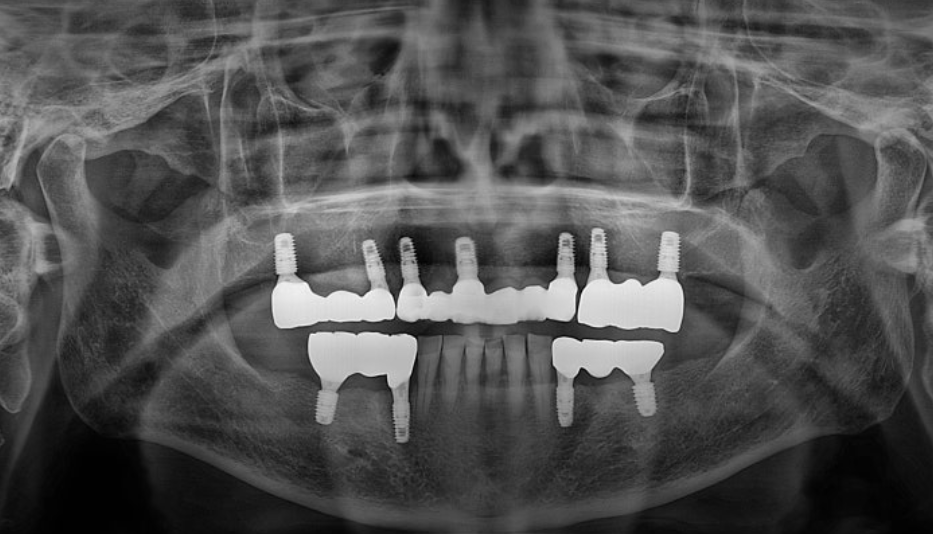

촬영일시 : 24.11.14 약 4개월 후 보철까지 완성된 엑스레이 사진입니다. 오늘은 수면 임플란트 치료라고도 흔히 알려진 의식하진정법을 이용한 임플란트 수술 증례를 소개해드렸습니다 ㅎㅎ 갯수가 많은 임플란트 수술에는 수면 임플란트 치료를 이용한다면 편안한 수술이 가능합니다. 지금까지 365일 열린 서울대학교 치과병원을 지향하는 도화역치과, 365서울앞선치과 대표원장 강동우였습니다. 감사합니다. [치료기간:2024년 6월12일 ~2024년 11월 14일] ※365서울앞선치과의원의 모든 포스팅은 각 진료과 의료진이 직접 작성합니다. 365서울앞선치과의원 블로그의 임상 케이스 게시물은 환자분께 의학적으로 정확하고 상세한 정보를 드리기 위해 각 진료과 의료진이 직접 작성하며, 모든 증례 사진은 본원 의료진이 직접 시술한 증례를 촬영한 것으로, 의료법 제23조, 제56조에 의거하며 환자분의 동의를 얻어 포스팅에 사용하였습니다. 또한 해당 케이스는 본 환자분의 치료 결과이며, 환자 상태에 따라 치료의 결과는 달라질 수 있습니다. |